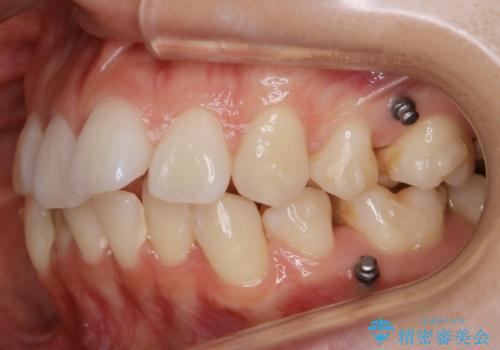

- 以前、中学生から高校生にかけてワイヤー装置による抜歯矯正を経験されている患者さんで、大人になってからのライフスタイルの変化でリテーナーを継続使用することができず、ガタつきが目立つようになってきてしまったのでもう一度矯正治療がしたいという主訴でご来院されました。

既に上下左右の4番目の歯が抜歯されているため、今回の治療では抜歯をせず歯の移動だけでガタつきを治す必要があり難易度が高くなっていました。

- 税込 ¥968,000- (インビザライン コンプリヘンシブパッケージ + マイクロインプラント費用)費用は治療当時の料金となります